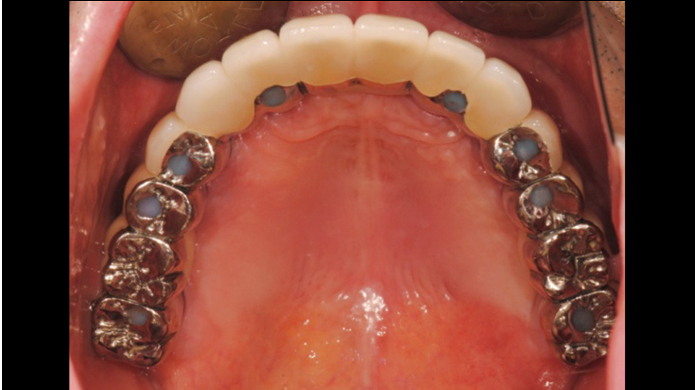

Clinical case: A Full transition from natural teeth to all-on-6 bridges

with AnyRidge implants

- Courtesy of Dr. Rabih Abi Nader, UAE -

Keywords

Full-mouth rehabilitation, minimal layering, Zirconia, all-on-6, life changing result, edentulous ,Dr. Rabih Abi Nader, AnyRidge

“AnyRidge shows excellent esthetic results

with Zirconia prosthesis in full-mouth rehabilitation case . ”